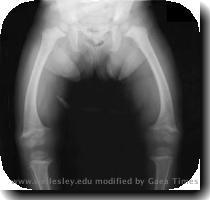

• » Rickets

rickets